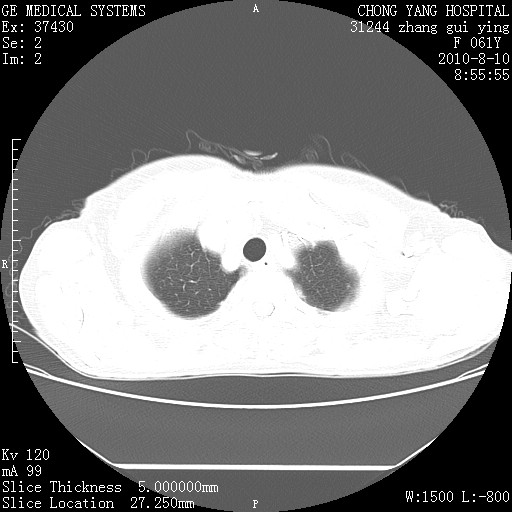

标题: CT28314:F61Y胸部增强,发热咳嗽一周入院,后面的为一周前平 [打印本页]

标题: CT28314:F61Y胸部增强,发热咳嗽一周入院,后面的为一周前平

1、支持考虑右侧中央型肺癌伴右肺中叶节段性不张及下叶支气管黏液痰栓    2、左肺上叶舌段感染。

支持右下肺中央型肺癌并左上肺感染.

双肺感染性病变,不除外合并结核感染。

确切的说:1:右肺下叶中心型肺癌侵及中叶支气管并中叶不张,纵膈淋巴结转移。2:左肺舌叶炎症。3:右侧胸腔少量积液

1:右肺下叶中心型肺癌侵及中叶支气管并中叶不张,纵膈淋巴结转移。2:左肺舌叶炎症。3:右侧胸腔少量积液。支持!

右肺下叶中心型肺癌侵及中叶支气管并中叶不张,纵膈淋巴结转移。2:左肺舌叶炎症。3:右侧胸腔少量积液